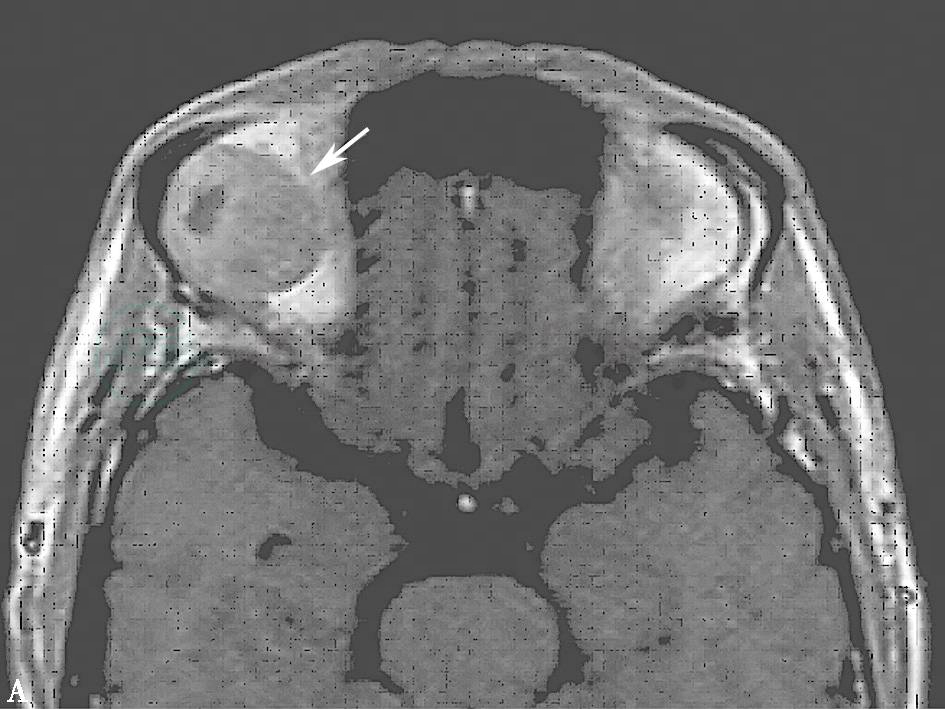

对多形性腺瘤的诊断无特异性,与其他良性肿瘤相似,T1WI显示为中信号,T2WI显示为中或高信号(图5),强化明显,可均匀一致强化或不均匀强化。肿瘤内出现大片液化区时,T1WI呈局灶低信号,T2WI为高信号,不能增强。复发性肿瘤为多个瘤体播散在眶软组织间,边界不清,信号不均,强化MRI显示尤为清晰。

图5 良性多形性腺瘤MRI

注:右侧泪腺区类圆形异常信号(箭头)。A.T1WI中信号,内有低信号斑点;B.T2WI中信号,内有高信号斑点。